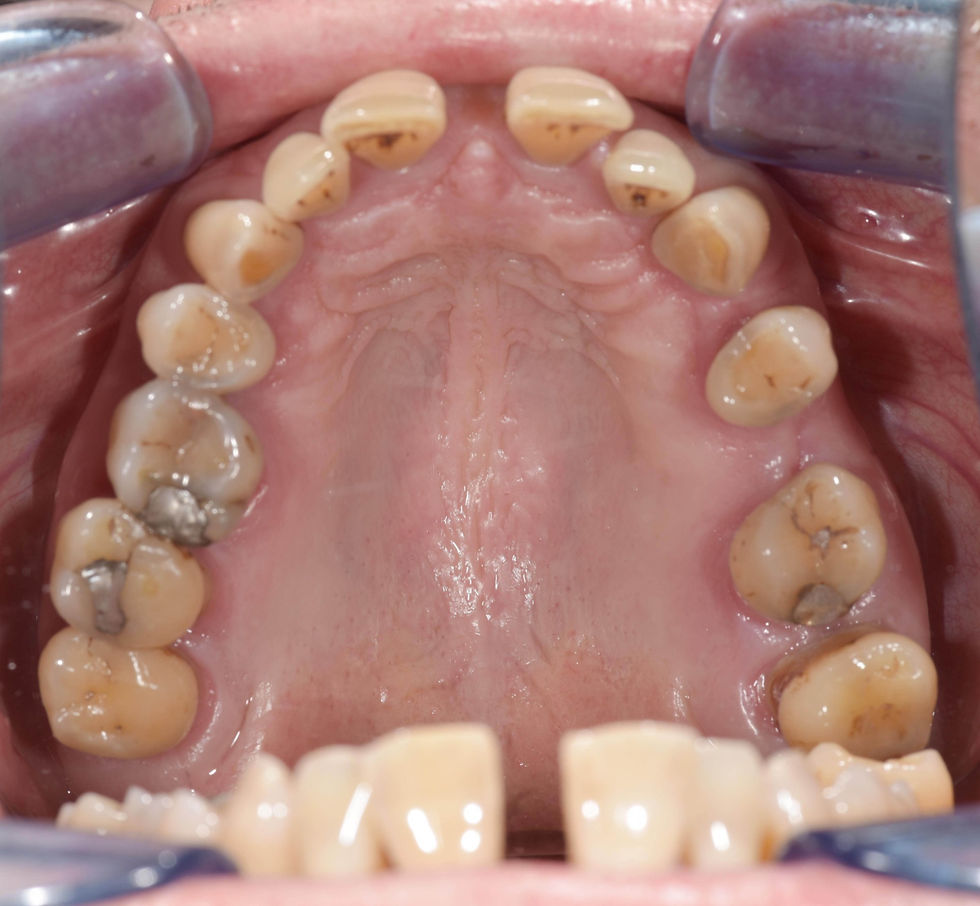

Initial situation: bone resorption is evident both in the maxilla and mandible.

Occlusal view of the preoperative case in which the resorption, both vestibular and lingual, of the lower arch is evident.

The movement of elements 2.4 and 2.6, following the loss of 2.5, also is noticeable.